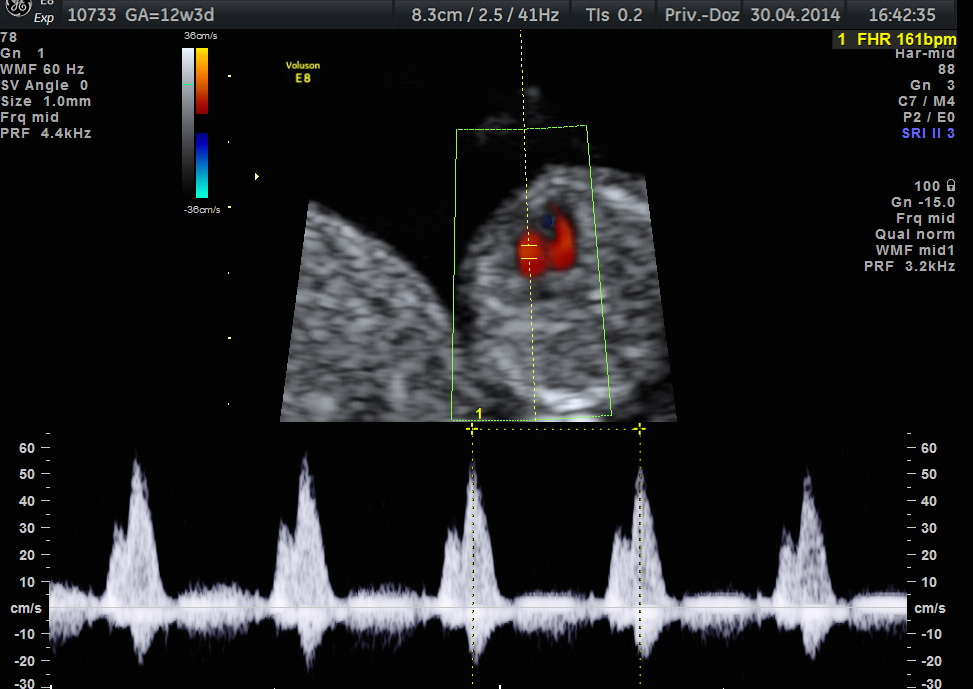

Normaler Blutfluss über die rechte Herzklappe (Trikuspitalklappe - TK) in der 13. Woche

Darstellung des TK in der 13. SSW mittels Farb-Doppler